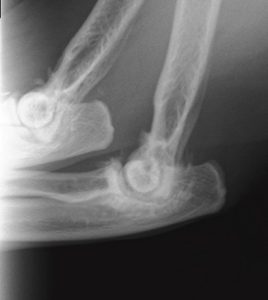

↑さつきちゃんの肘のレントゲン写真

肘の関節の骨がボコボコと変形しています